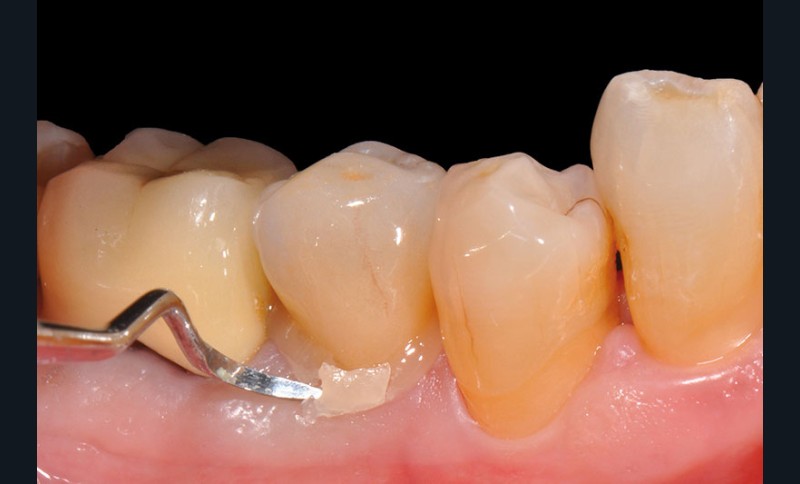

3, 4, 5. La restauration est déposée, les tissus carieux éliminés et la cavité d’accès aménagée avant la réalisation du traitement endodontique. La radiographie postopératoire permet de visualiser l’obturation du canal latéral en regard de la LIPOE.